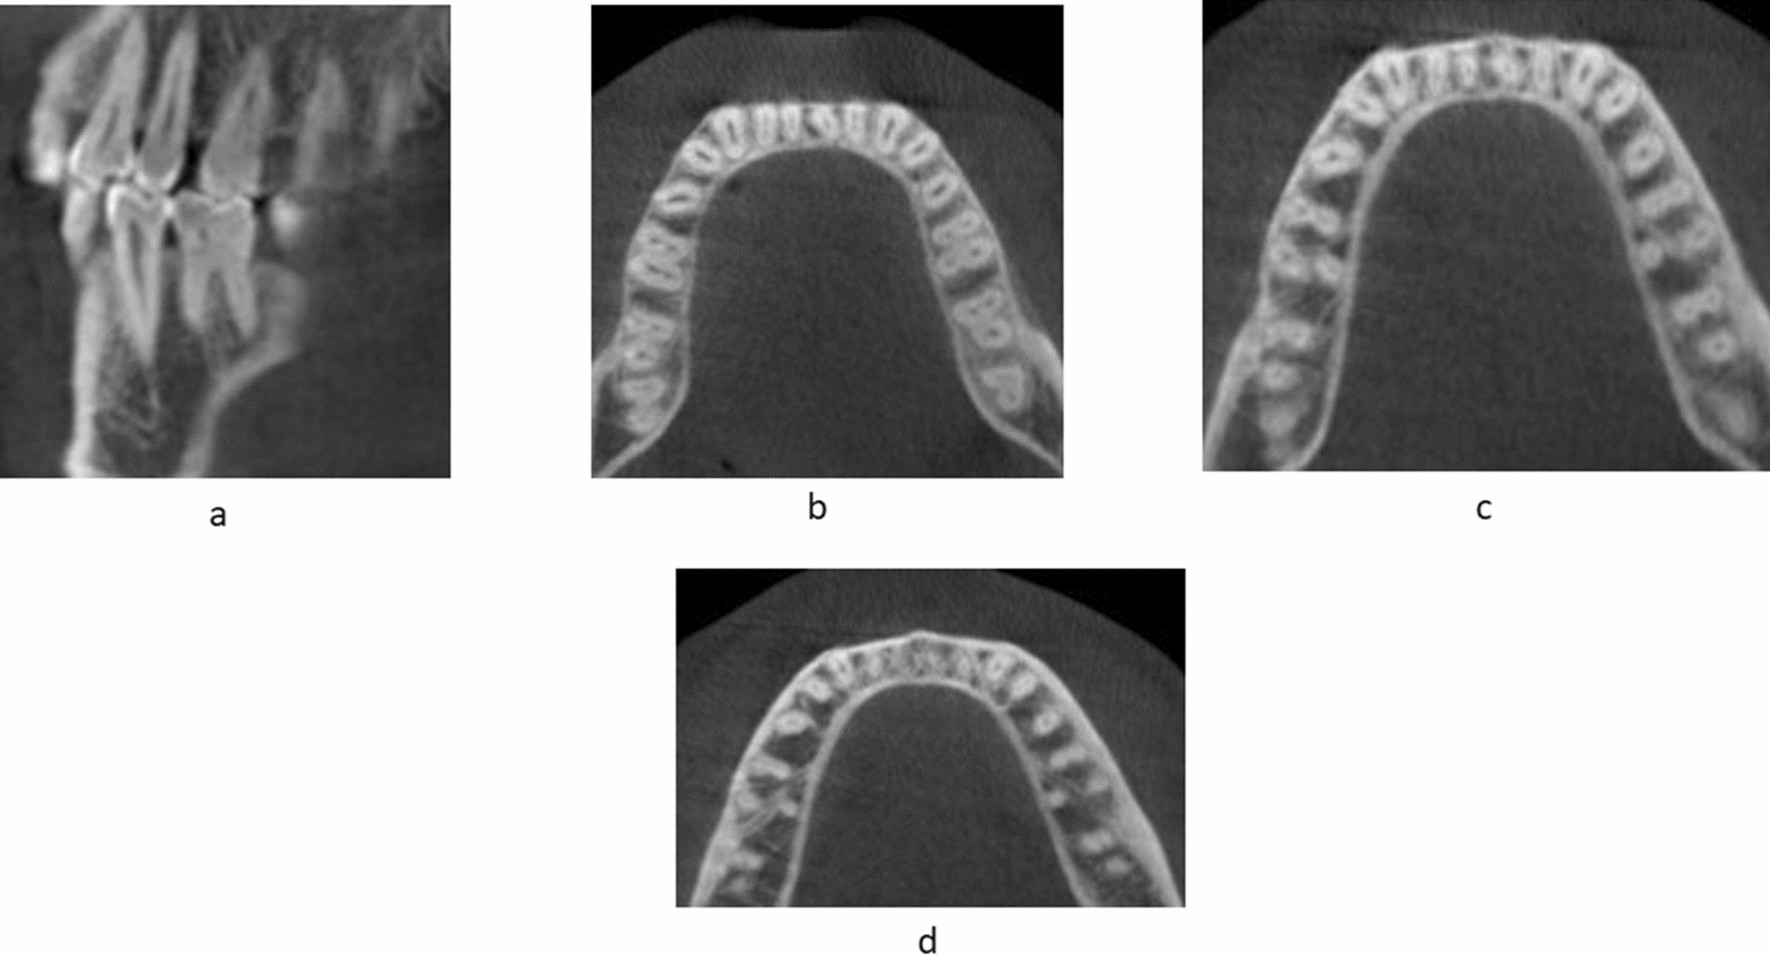

Figure 4

CBCT scans showing DLR in MFMs through various sections from coronal to apical. (a) Sagittal section of mandibular first molar. (b) Coronal third section of the axial view. (c) Middle third section of the axial view. (d) Apical third section of the axial view.